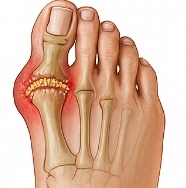

통풍 증상은 혈중 요산이 과다해져 관절에 요산 결정이 쌓이면서 발생하는 대표적인 대사 질환입니다. 통풍 증상은 발가락, 발등, 발목, 무릎 등의 극심한 통증으로 시작되며, 심한 경우 만성 관절 손상으로 이어질 수 있습니다. 오늘은 통풍 증상 10가지와 통풍의 원인, 초기 진단, 치료 및 관리법까지 구체적으로 안내해드리겠습니다.

통풍은 혈액 속 요산 수치가 높아져 결정 형태로 관절에 침착되어 염증을 유발하는 질환입니다. 통풍 증상은 대부분 발가락 관절에서 시작되며, 특히 밤에 갑작스럽게 심한 통증이 나타나는 것이 특징입니다. 통풍은 단순한 관절염이 아닌 요산 대사 이상 질환으로, 식습관과 생활습관이 큰 영향을 미칩니다. 통풍 증상은 초기에는 가벼운 부기나 열감으로 시작되지만, 시간이 지나면 관절이 변형되고 통증이 만성화될 수 있습니다.

통풍 증상 중 가장 대표적인 것은 관절 부위의 극심한 통증과 붓기입니다. 대개 밤이나 새벽에 갑자기 찾아오며, 통증이 너무 심해 이불이 닿기만 해도 견디기 힘든 수준입니다. 통풍 증상은 주로 엄지발가락에서 시작하지만, 발목·무릎·손가락 등 다른 관절로도 퍼질 수 있습니다. 초기에는 2~3일 후 통증이 가라앉지만, 재발을 반복할수록 통증 기간이 길어지고 염증이 심해집니다.

통풍 증상에서는 통증뿐 아니라 열감과 붉은 피부색 변화가 동반됩니다. 염증이 심해지면 해당 부위의 온도가 올라가고, 손으로 만지면 뜨겁게 느껴집니다. 통풍 증상은 염증 반응이 활발할 때 발목, 발등, 손가락 관절 등이 붉고 붓는 양상으로 나타납니다.